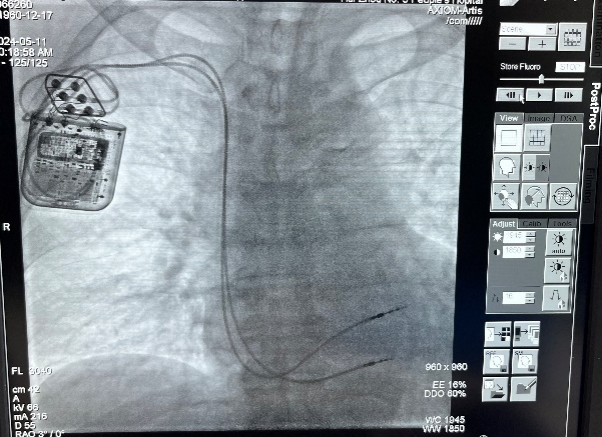

楊飛主任(右)手術(shù)中

在楊飛主任醫(yī)師、方永有副主任醫(yī)師及科室人員的密切配合下,手術(shù)如期進(jìn)行。憑借豐富的操作經(jīng)驗(yàn)和精湛的導(dǎo)線操控技術(shù),手術(shù)團(tuán)隊先后植入兩根主動起搏電極置于右室間隔。經(jīng)過測試,植入患者體內(nèi)的調(diào)節(jié)器各項參數(shù)良好,電極準(zhǔn)確植入到了健康心肌上,發(fā)出持續(xù)、穩(wěn)定的信號,陳叔各項生命體征平穩(wěn)。未來,CCM可通過體外充電器,長期持續(xù)為陳叔提供治療,通過逆轉(zhuǎn)心室重構(gòu)的長期作用,改善心功能,提高生活質(zhì)量。